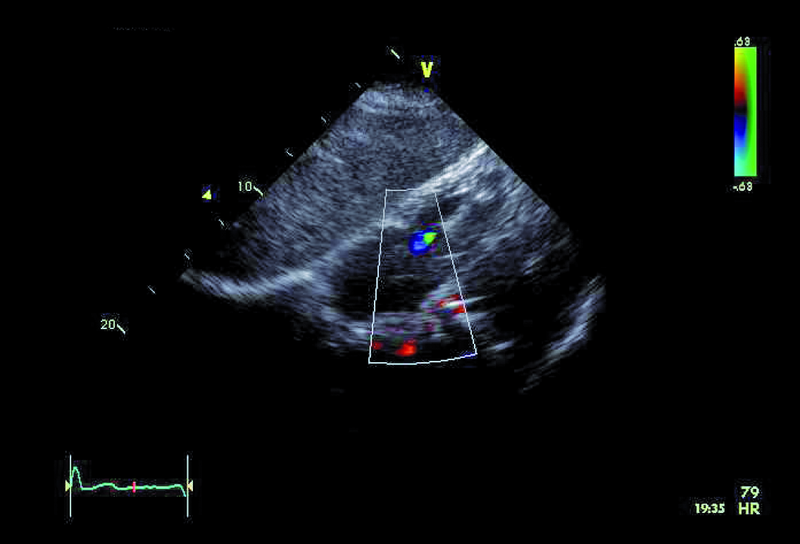

4. Mała niedomykalność zastawki trójdzielnej (ryc. 4-6).

5. Mały ubytek przegrody międzykomorowej z lewo-prawym przeciekiem (ryc. 5).

6. Istotne nadciśnienie płucne (ryc. 6).